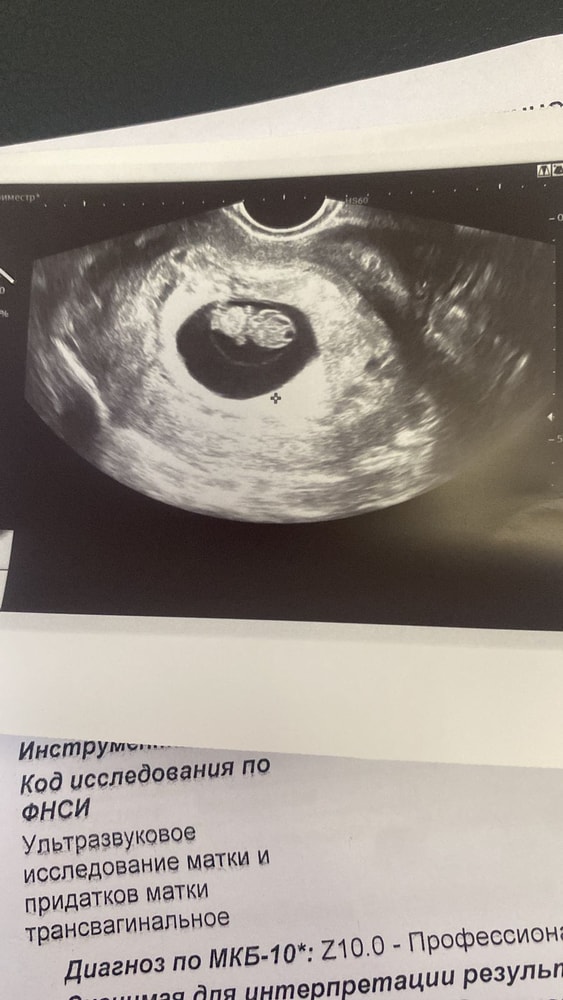

41 ДПП не выдержала сходила на узи

Результаты УЗИ

Выросли мы очень хорошо, все у нас в порядке, сердечко бьётся 178 уд/мин, послушали и записала на видео! Малыш очень хорошо подрос, голова, ручки, ножки, даже показали что он уже дрыгается, какое же это счастье!